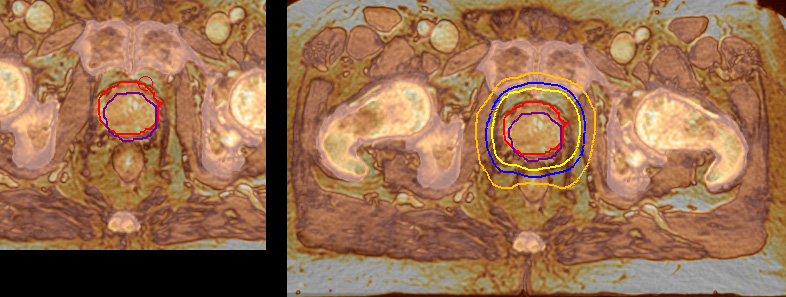

“The biggest problem for CT-based planning, especially in prostate, is you can’t see the cancer very well,” says Dr. Stevens. “On CT it can be quite challenging to see the edge of the prostate especially at the apex. When the edge of the prostate can’t be delineated well on CT, radiation oncologists will increase their margins a little bit so they don’t miss it, but that can also increase toxicity.” “Using MR, the prostate is well delineated. We quickly see the edges of cancerous tumors like in prostate cancer, and as normal structures can be defined, we can optimize the treatment plan to protect these organs and their normal function. This can potentially improve the outcome. And it improves workflow as well. We can contour more quickly, confident that the tumor is going to be in the field.” “The Ingenia 3.0T MR scanner provides high resolution allowing us to make scans fast for the patients. It also gives the potential to include methods like MR spectroscopy and diffusion weighted Imaging, which we’re in the process of doing right now,” Dr. Stevens adds.

“When a patient registers, first CT simulation and MR simulation are done, followed by CT-MR registration on Pinnacle3. Then the target and normal organ delineation is performed on MR images. Meanwhile we create a reference CT image for online treatment and localization correction. During the treatment phase we can perform additional MRI scans to visualize the anatomy changes and create an adaptive plan. This plan basically adapts the treatment plan to the changes.” “Along with its great benefits, MR has introduced some new challenges,” Dr. Stevens says. “Radiation therapy teams generally have no experience with MR. The Philips training helped us to implement fully the things we can do with the Ingenia MR-RT system. So the training, as well as having a good MR physicist, is critical.”